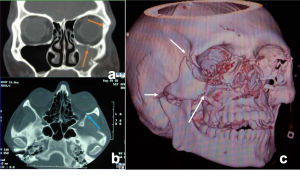

Most frequent involvement IR>MR>SR>LR. Superior Ophthalmic Vein may be enlarged due to apical compression | Axial and coronal section of non-contrast CT images of orbit showing three different patterns of TED. a) Bilateral fusiform enlargement of the extraocular muscles sparing the tendinous insertion with posterior crowding (orange stars) b) Bilateral fusiform enlargement of the extraocular muscles sparing the tendinous insertion along with increased orbital fat. c) Bilateral increased orbital fat (denoted by increase of hypodense areas of fat attenuation). EOM appears normal. |